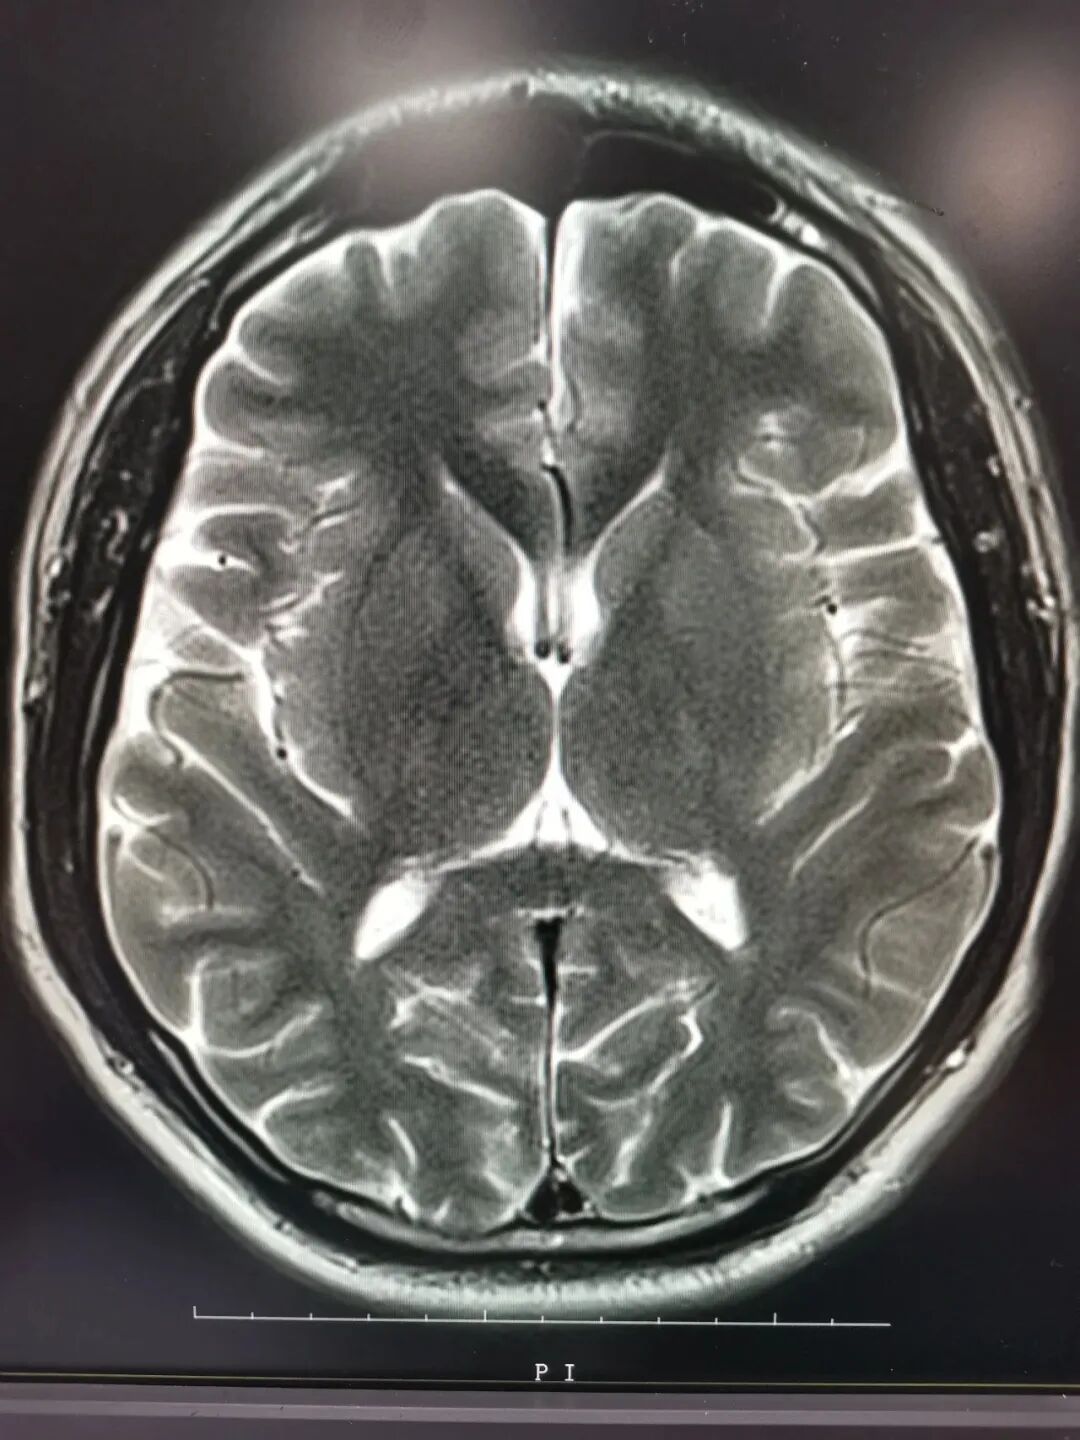

核磁共振 摇一摇再看

核磁共振机使用较强大的磁场,使人体中所有水分子磁场的磁力线方向一致,这时磁共振机的磁场突然消失,身体中水分子的磁力线方向,突然恢复到原来随意排列的状态。简单说就相当于用手摇一摇,让水分子振动起来,再平静下来,找出有问题的振动。所以,核磁共振(MRI)也被戏说为是摇摇看的检查。

磁共振软组织显示好。

磁共振检查时间长,对钙化及骨质显示不好。体内有铁磁性植入物(比如人工关节,人工瓣膜,动脉银夹)不能做磁共振。

2、颈椎腰椎——最佳选核磁,次选CT。

颈椎病、腰椎间盘突出等椎间盘疾病需要观察椎间盘与相应的神经根,要想更好观察这些软组织,最优选择就是核磁。同样,对于大脑、四肢关节、肌肉、脂肪组织检查,核磁也是首选。